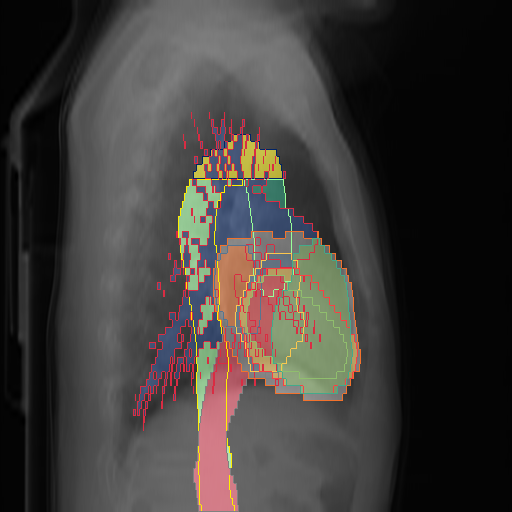

We show qualitative results for frontal projections in Fig. 2. We show a subset of classes belonging to the supercategories lungs, vascular systems, bones, and abdomen/digestive system. The predictions show minor deviations at the boundaries of the individual classes of the respiratory and vasculature system, while some inaccuracies become visible in the abdominal area. The qualitative results for the lateral projections are displayed in Fig. 2. Akin to the frontal view, the predictions show smoother borders but align with the ground truth. Apart from this, the segmentations provide matching insights on the thoracic anatomy with a slight deviation from the ground truth for both frontal and lateral views.

We display qualitative results in Fig. 3. The annotators tend to be content with most annotations. There are edits at the extensions of the esophagus, trachea, and aorta and corrections of the lower ribs. There is little consensus for classes in the abdominal area, such as the stomach, as seen on the right of Fig. 3 . In contrast, the annotators often align for bone classes.